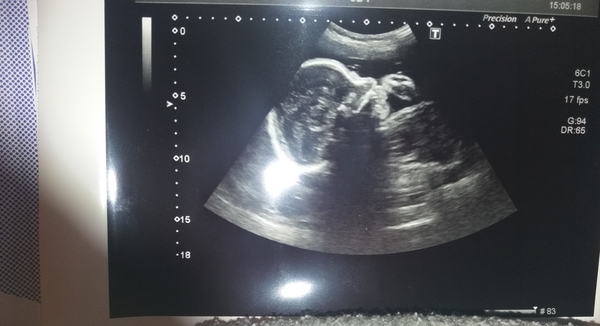

I'm relieved to say that my little dude is doing well, his growth is fine and no concerns even though my bump is small. Here he is!

More Christmas Cake! Pregnancy after loss (thread 3)